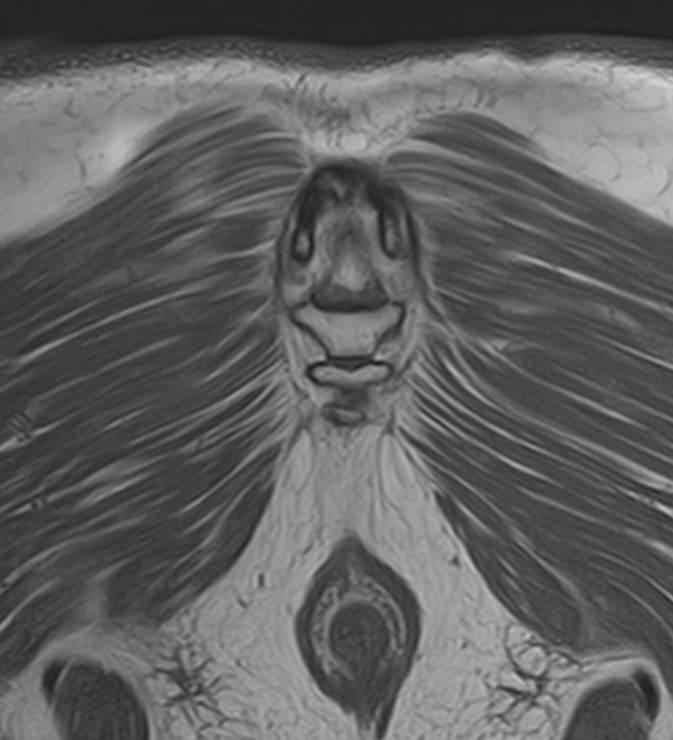

Магнитно-резонансная томография является наиболее чувствительным и эффективным методом диагностики различных заболеваний позвоночника. Метод позволяет оценить состояние костных структур позвонков, позвоночного канала с расположенным в нем спинным мозгом и окружающих мягких тканей, кроме того является основным способом диагностики демиелинизирующих заболеваний спинного мозга.

• Боли в области копчика (кокцигодиния), которая часто сочетается с заболеваниями органов малого таза.

Что покажет МРТ всего позвоночника – 3 отдела + копчик

Данное комплексное обследование позволяет выявить следующие патологические состояния:

• Аномалии развития позвоночника.